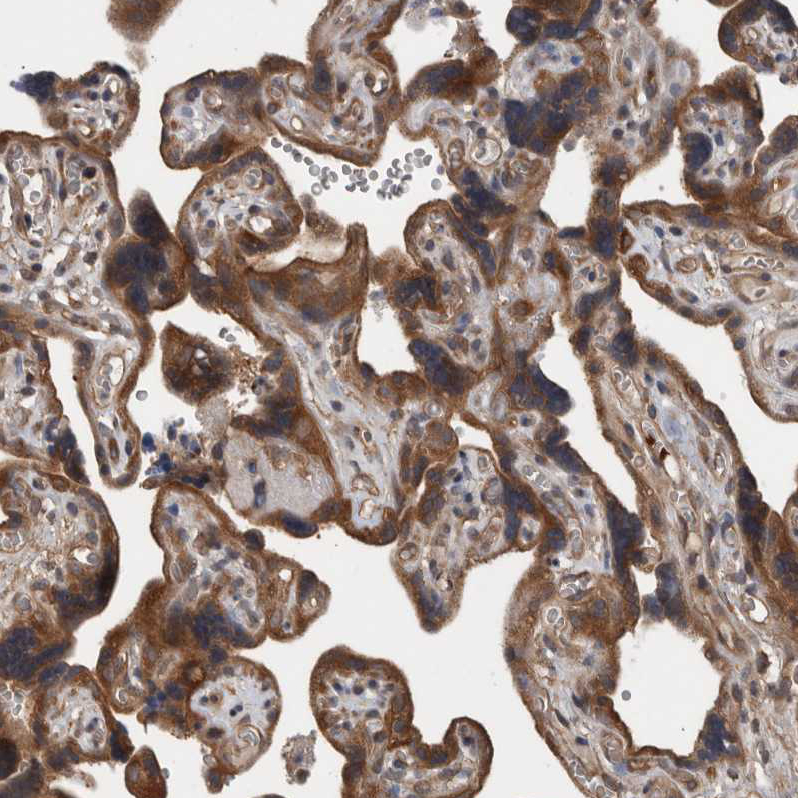

Immunohistochemical staining of human Placenta shows moderate cytoplasmic positivity in trophoblastic cells.